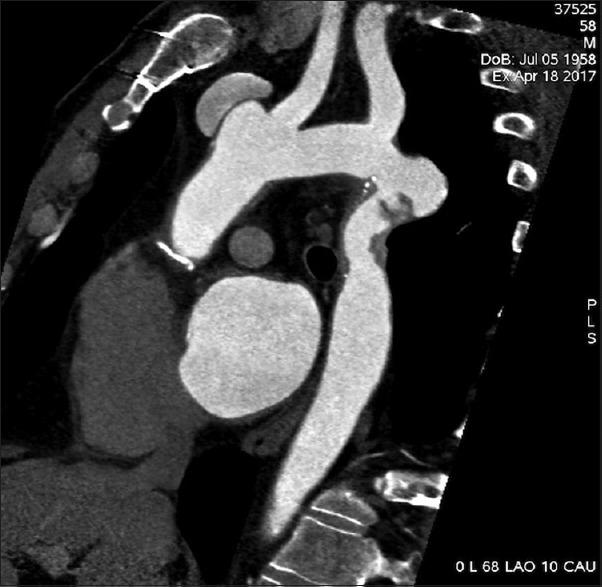

成人术后缩窄性假性动脉瘤血管腔内修复术中主动脉破裂:紧急植入挽救生命的覆膜支架。

Aortic rupture during endovascular repair of a postoperative coarctation pseudoaneurysm in an adult: Emergency lifesaving stent graft implantation.

We present a case with aortic rupture during an operation of thoracic endovascular aortic repair of an anastomotic pseudoaneurysm. This happened after the use of a low-pressure remodeling balloon inside the covered part of the deployed endografts. It was successfully treated with a second more centrally in the aortic arch-implanted endograft with full coverage of the left subclavian artery orifice. This patient had a history of surgically operated aortic coarctation.

摘要

我们报告一例在胸主动脉腔内修复吻合口假性动脉瘤手术过程中发生主动脉破裂的病例。这发生在已植入的覆膜支架移植物覆盖部分内使用低压重塑球囊之后。通过在主动脉弓更中心位置植入第二个完全覆盖左锁骨下动脉开口的支架移植物成功治疗了该病例。该患者有主动脉缩窄手术史。